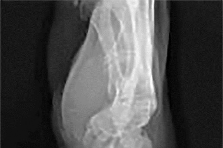

A 68-year-old osteoporotic female sustains a proximal humerus fracture. The AP radiograph is shown. According to the Hertel criteria, which of the following radiographic features is the most reliable predictor of humeral head ischemia?

Options:

Correct Answer: Metaphyseal head extension (calcar segment) less than 8 mm

Explanation:

Hertel et al. described radiographic criteria predictive of humeral head ischemia. The most reliable predictors include a metaphyseal head extension (calcar segment) of less than 8 mm, disruption of the medial hinge (>2 mm), and an anatomic neck fracture. Among the choices, the calcar segment length < 8 mm represents a highly predictive sign that the primary blood supply (the ascending branch of the anterior humeral circumflex artery and intraosseous vessels) has been severely compromised.